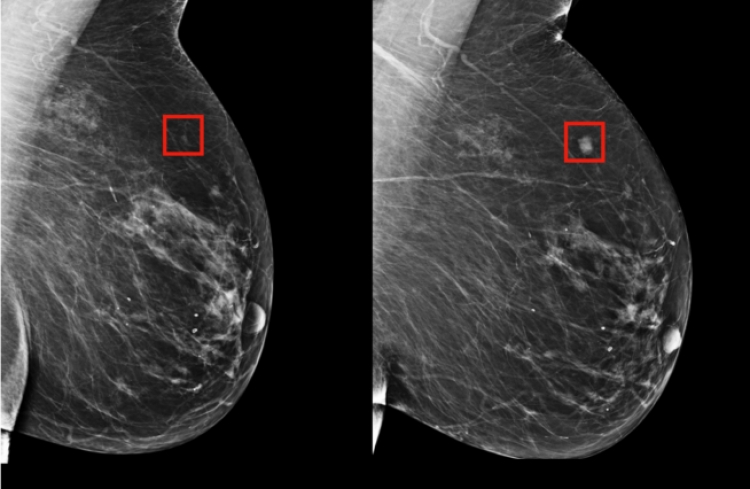

The team, which included researchers at Imperial College London and Britain’s National Health Service, trained the system to identify breast cancers on tens of thousands of mammograms. They then compared the system’s performance with the actual results from a set of 25,856 mammograms in the United Kingdom and 3,097 from the United States.

The study showed the AI system could identify cancers with a similar degree of accuracy to expert radiologists while reducing the number of false-positive results by 5.7 percent in the US-based group and by 1.2 percent in the British-based group.

It also cut the number of false negatives, where tests are wrongly classified as normal, by 9.4 percent in the US group, and by 2.7 percent in the British group.